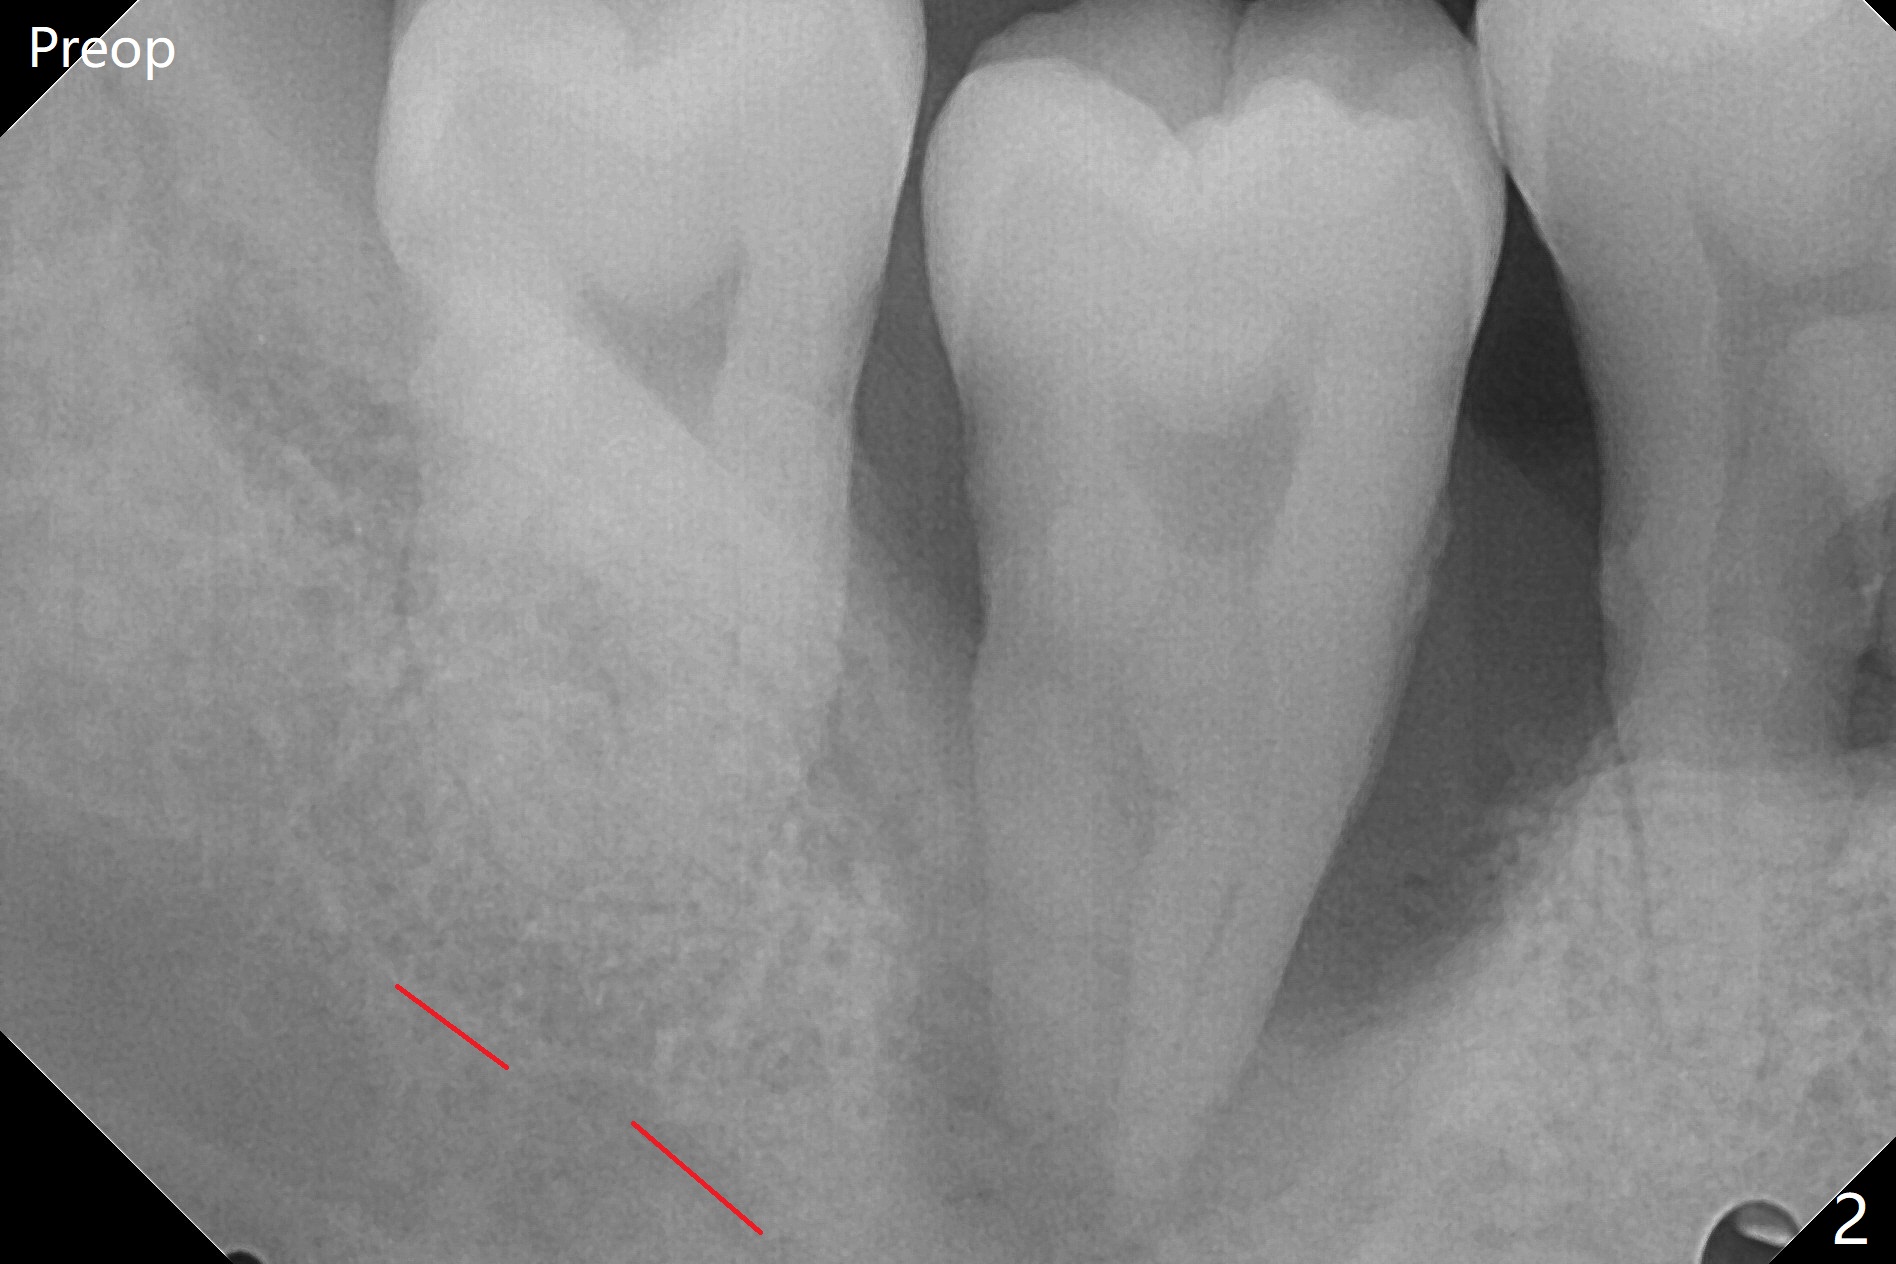

40岁男,牙周炎(图一,4年前拍摄),现在要求拔除31号牙,劝导后同意植骨,问题在于牙根长(图二),可能接近神经(红虚线)。拔牙后,舌侧骨板缺失,不敢大胆在根尖清创,术中拍摄根尖片(图三),牙槽窝根尖接近神经管,最后可能遗留些根尖肉芽组织(图四:*(最好拍摄CT))。粘性骨粉表面覆盖PRF和Cytoplast,使用4-0 PTFE缝线,没有使用牙周敷料,因为后者往往与缝隙粘连,脱落时缝线必须撤除,可能影响不可吸收膜固定。不过这次不可吸收膜术后四天脱落,术后五天骨粉好像丢失不多(图五),可能与粘性骨粉有关。下次需要牙周敷料,牙齿长,敷料固定好。Return to Protect Graft 19 位点保存 Xin Wei, DDS, PhD, MS 1st edition 06/28/2021, last revision 07/09/2021